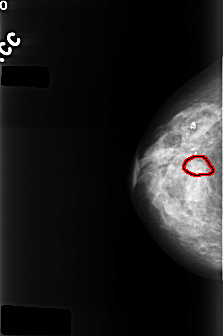

C_0394_1.RIGHT_CC

RIGHT_CC LINES 4368 PIXELS_PER_LINE 2904 BITS_PER_PIXEL 12 RESOLUTION 50 OVERLAY

FILE: C_0394_1.RIGHT_CC.OVERLAY

TOTAL_ABNORMALITIES 1

ABNORMALITY 1

LESION_TYPE CALCIFICATION TYPE AMORPHOUS DISTRIBUTION CLUSTERED

ASSESSMENT 4

SUBTLETY 2

PATHOLOGY BENIGN

TOTAL_OUTLINES 1

BOUNDARY